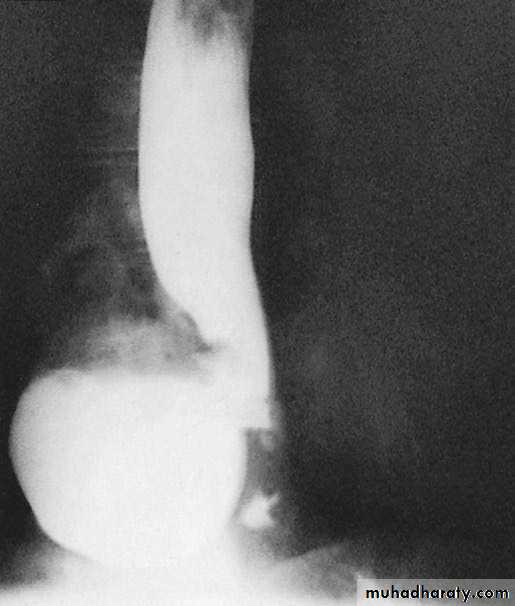

Figure1 : large filling defect by GIST.